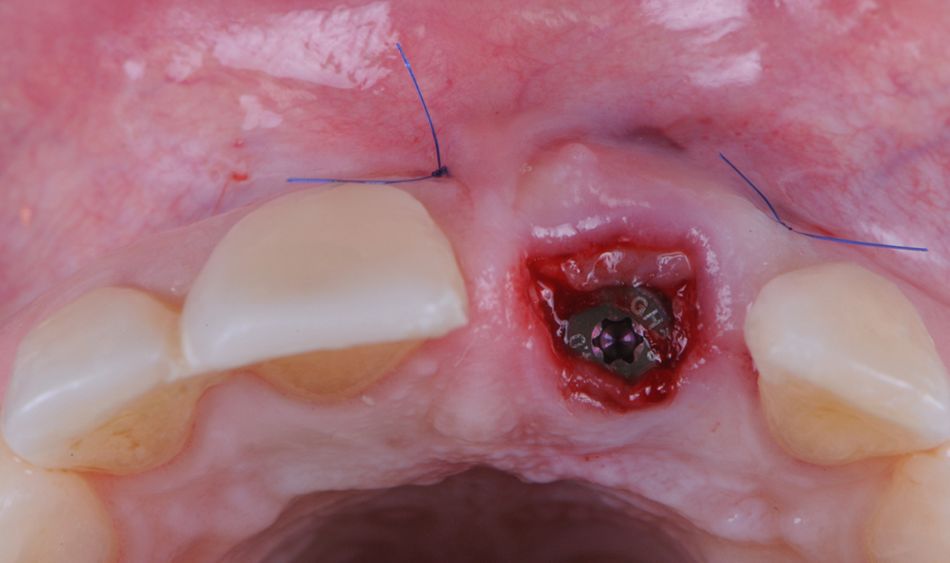

To eliminate any inflammatory or infectious tissue that may have remained in the socket, the periapical region was carefully curetted, and extensive irrigation was performed with normal saline. The freehand and flapless surgery involved the immediate placement of a Straumann® BLX Implant ∅ 3.75 mm - Regular Base -SLActive® 12 mm Roxolid® in position #21 following the manufacturer's instructions to ensure primary stability (Figs. 16-20). The drilling was located on the center of the extraction socket in the palatal wall, and the implant site was to the palatal side in a prosthetic-driven position.

Primary implant stability was achieved, and a prefabricated titanium temporary abutment (Straumann® RB/WB Temporary Abutment) was subsequently hand-tightened onto the implant for instant provisionalization. The height of the temporary abutment was measured and the abutment was removed and adjusted extraorally (Fig. 21).Next, the temporary abutments were reseated into the implant, hand-tightened, and the height was rechecked (Fig. 22).

The healing abutment was placed and screwed prior to the graft transplantation (Fig. 24).

A subepithelial connective tissue graft was obtained from the palate and was adapted onto the recipient site with the aim of increasing the thickness of the keratinized mucosa. Lastly, the graft was fixed with 5-0 nylon interrupted sutures (Fig. 25). The provisional crown was then screwed into the implant, and the access hole was sealed (Figs. 26,27).